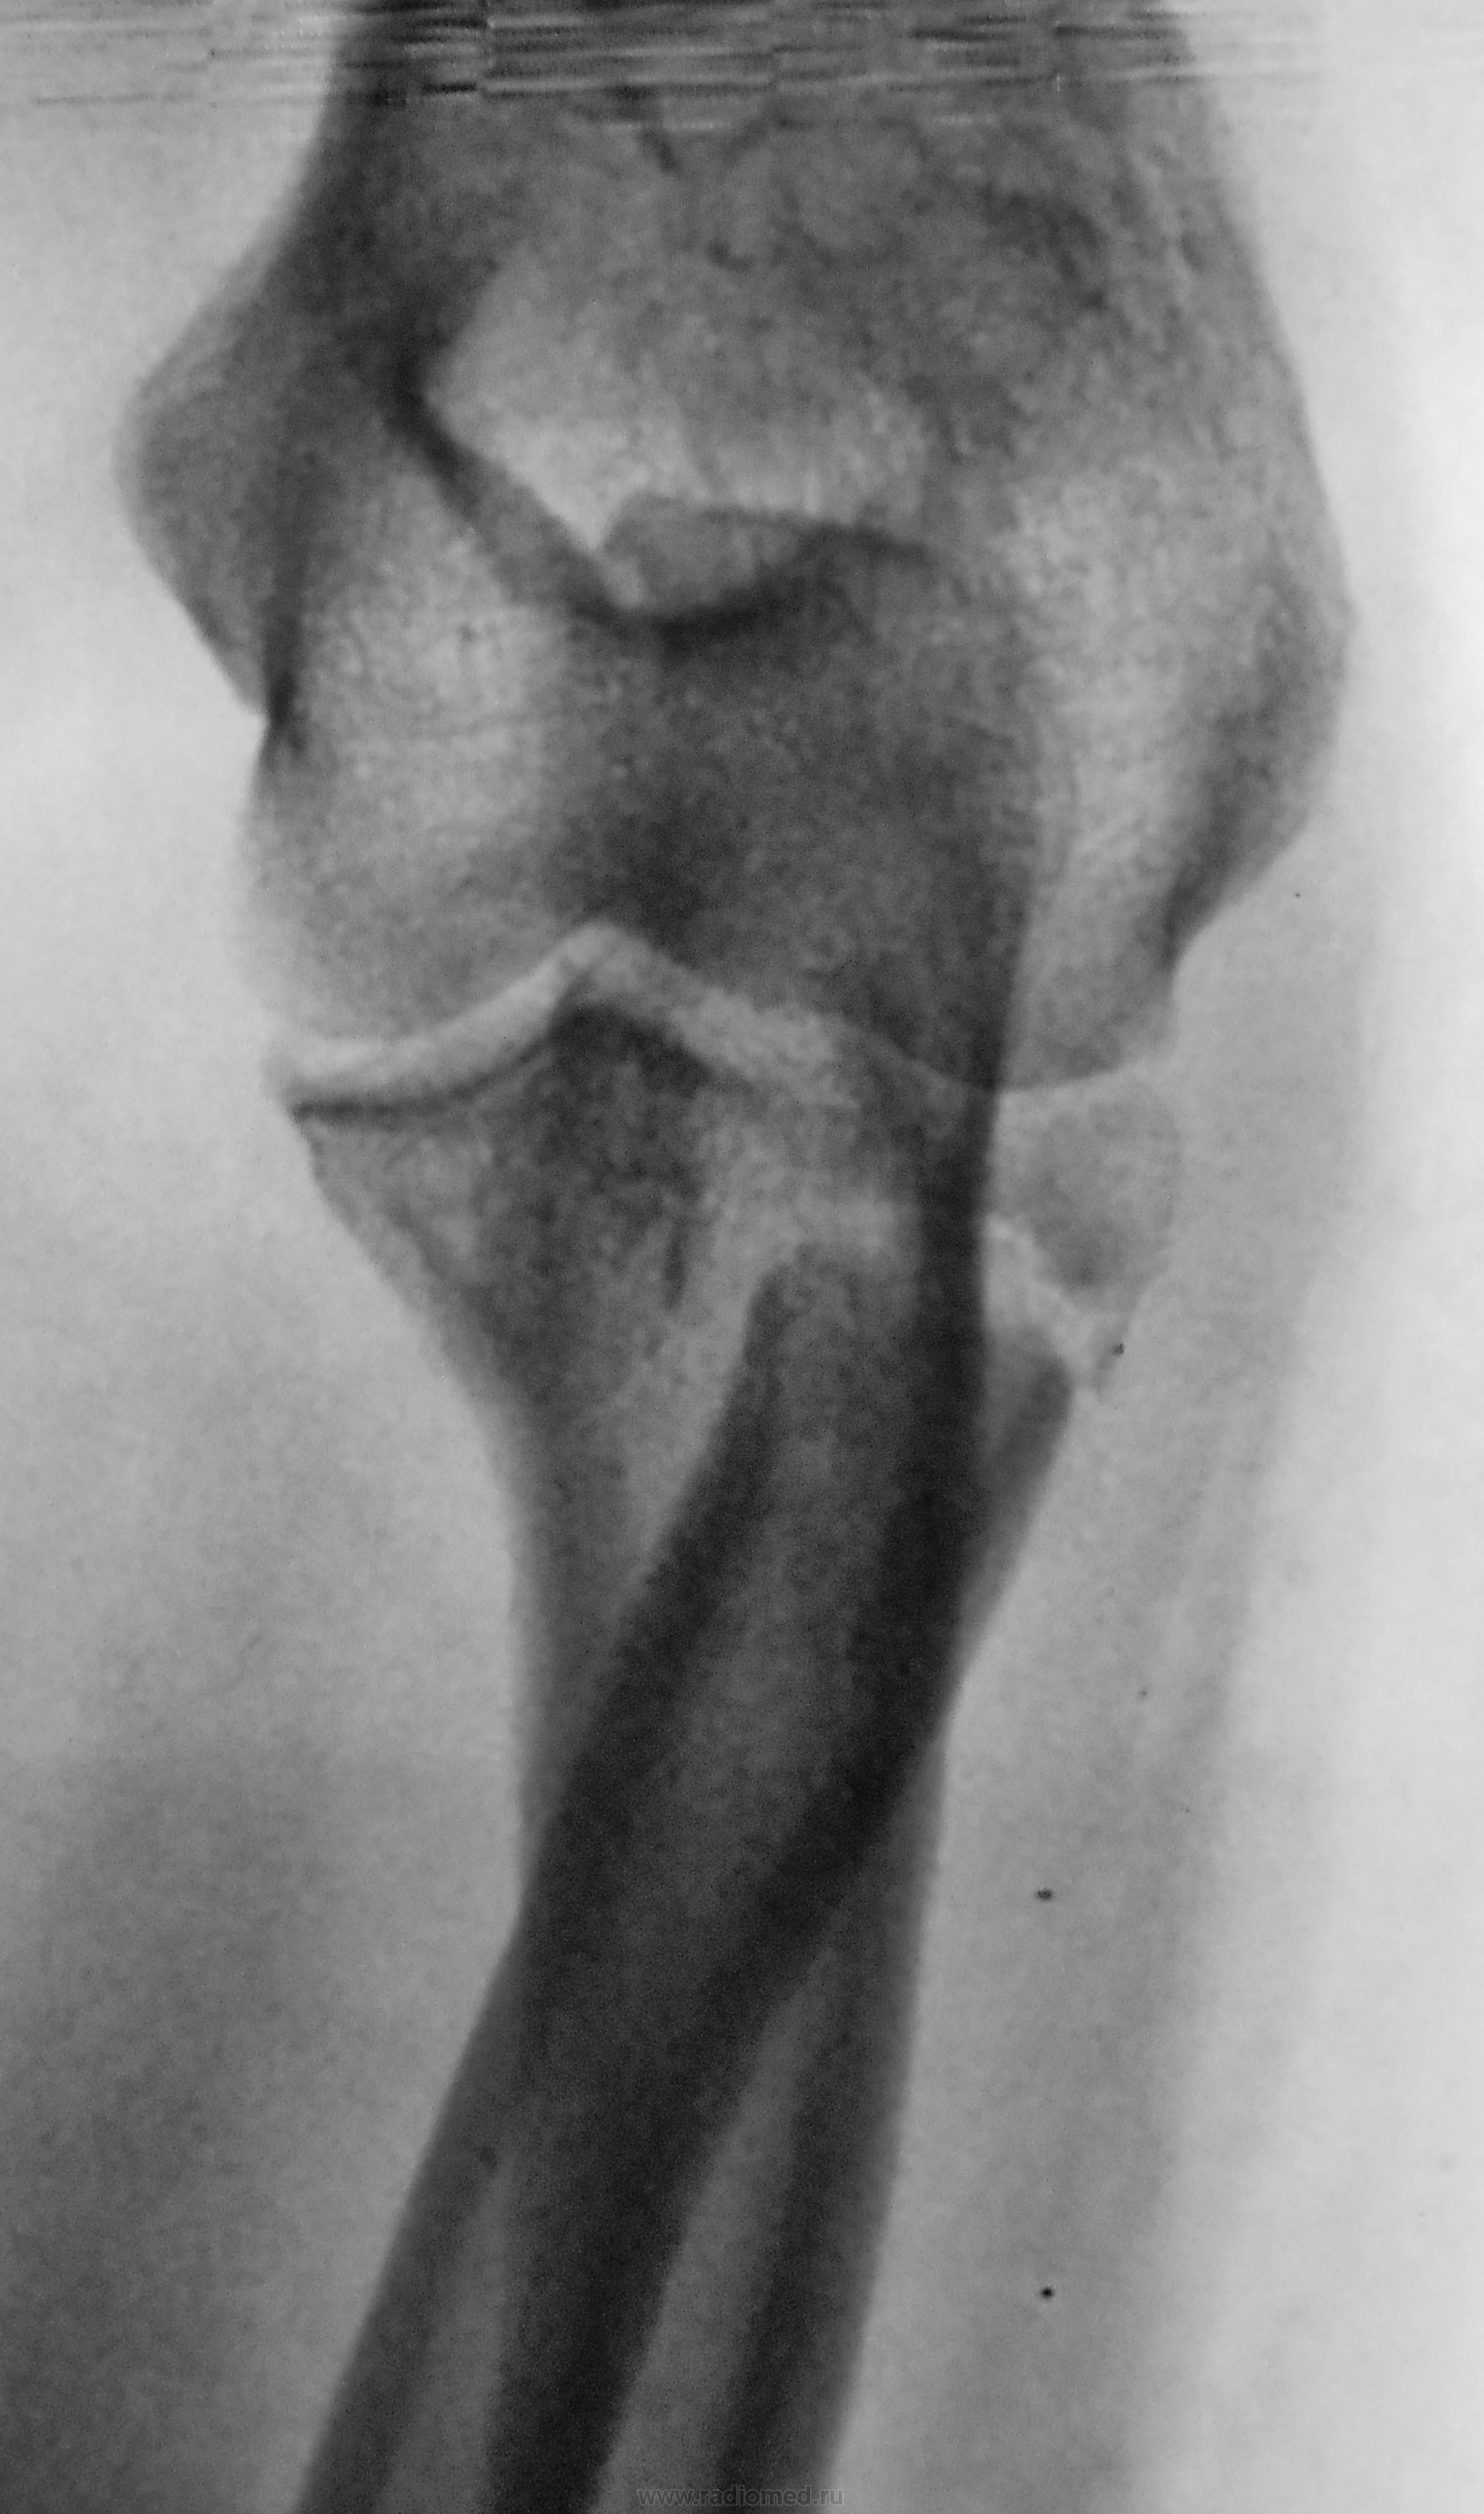

Пол пациента: Женский пол Тип патологии: Травма Область исследования: Скелетно-мышечная система Методы исследования: Rg После лечения направлен на рентген-контроль для подтверждения консолидации https://radiomed.ru/sites/default/files/styles/case_slider_image/public/user/12/2.dscn1622a.jpg?itok=S1eF-zXd https://radiomed.ru/sites/default/files/styles/case_slider_image/public/user/12/3.dscn1623.jpg?itok=X2Hg0JZv https://radiomed.ru/sites/default/files/styles/case_slider_image/public/user/12/4.dscn1623a.jpg?itok=NNPpyqMN ID:28492 Tue, 14/05/2013 - 22:50 #1 Сергей Кузьминов Offline Last seen: 1 year 2 months ago Joined: 06.10.2012 - 15:51 Posts: 11813 Не подтверждается консолидация. Tue, 14/05/2013 - 23:52 #2 И.Бондаренко Offline Last seen: 16 hours 36 min ago Joined: 13.09.2011 - 22:55 Posts: 9208 А как было вначале лечения? Wed, 15/05/2013 - 15:31 #3 Катенёв Валенти... Offline Last seen: 7 years 2 months ago Joined: 22.03.2008 - 22:15 Posts: 54876 Первичных снимков нет. Были сделаны в областном центре, там и остались, наруки не выдали. Thu, 16/05/2013 - 20:49 #4 Роман Муравьев Offline Last seen: 4 years 11 months ago Joined: 02.10.2010 - 20:09 Posts: 191 А это чего? отломок от головки лучевой так сместился?Приложения:

Не подтверждается консолидация.

А это чего? отломок от головки лучевой так сместился?